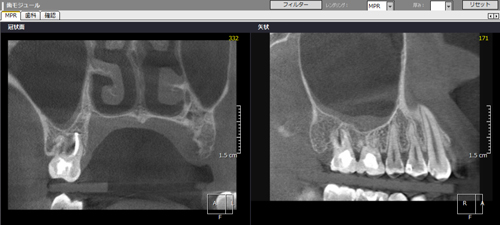

2Dのレントゲンではわずかな病巣としか見えませんが、3DのCTでは内部にかなり大きな病変が在るのが良くわかります。

治療前

治療後